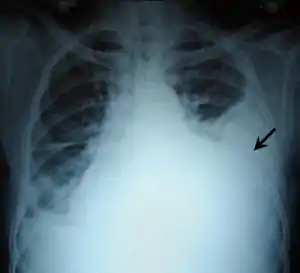

A pleural effusion appears as an area of whiteness on a standard posteroanterior chest X-ray.[12] Normally, the space between the visceral pleura and the parietal pleura cannot be seen. A pleural effusion infiltrates the space between these layers. Because the pleural effusion has a density similar to water, it can be seen on radiographs. Since the effusion has greater density than the rest of the lung, it gravitates towards the lower portions of the pleural cavity. The pleural effusion behaves according to basic fluid dynamics, conforming to the shape of pleural space, which is determined by the lung and chest wall. If the pleural space contains both air and fluid, then an air-fluid level that is horizontal will be present, instead of conforming to the lung space.[13] Chest radiographs in the lateral decubitus position (with the patient lying on the side of the pleural effusion) are more sensitive and can detect as little as 50 mL of fluid. Between 250 and 600mL of fluid must be present before upright chest X-rays can detect a pleural effusion (e.g., blunted costophrenic angles).[14]

Massive left-sided pleural effusion (whiteness) in a patient presenting with lung cancer.